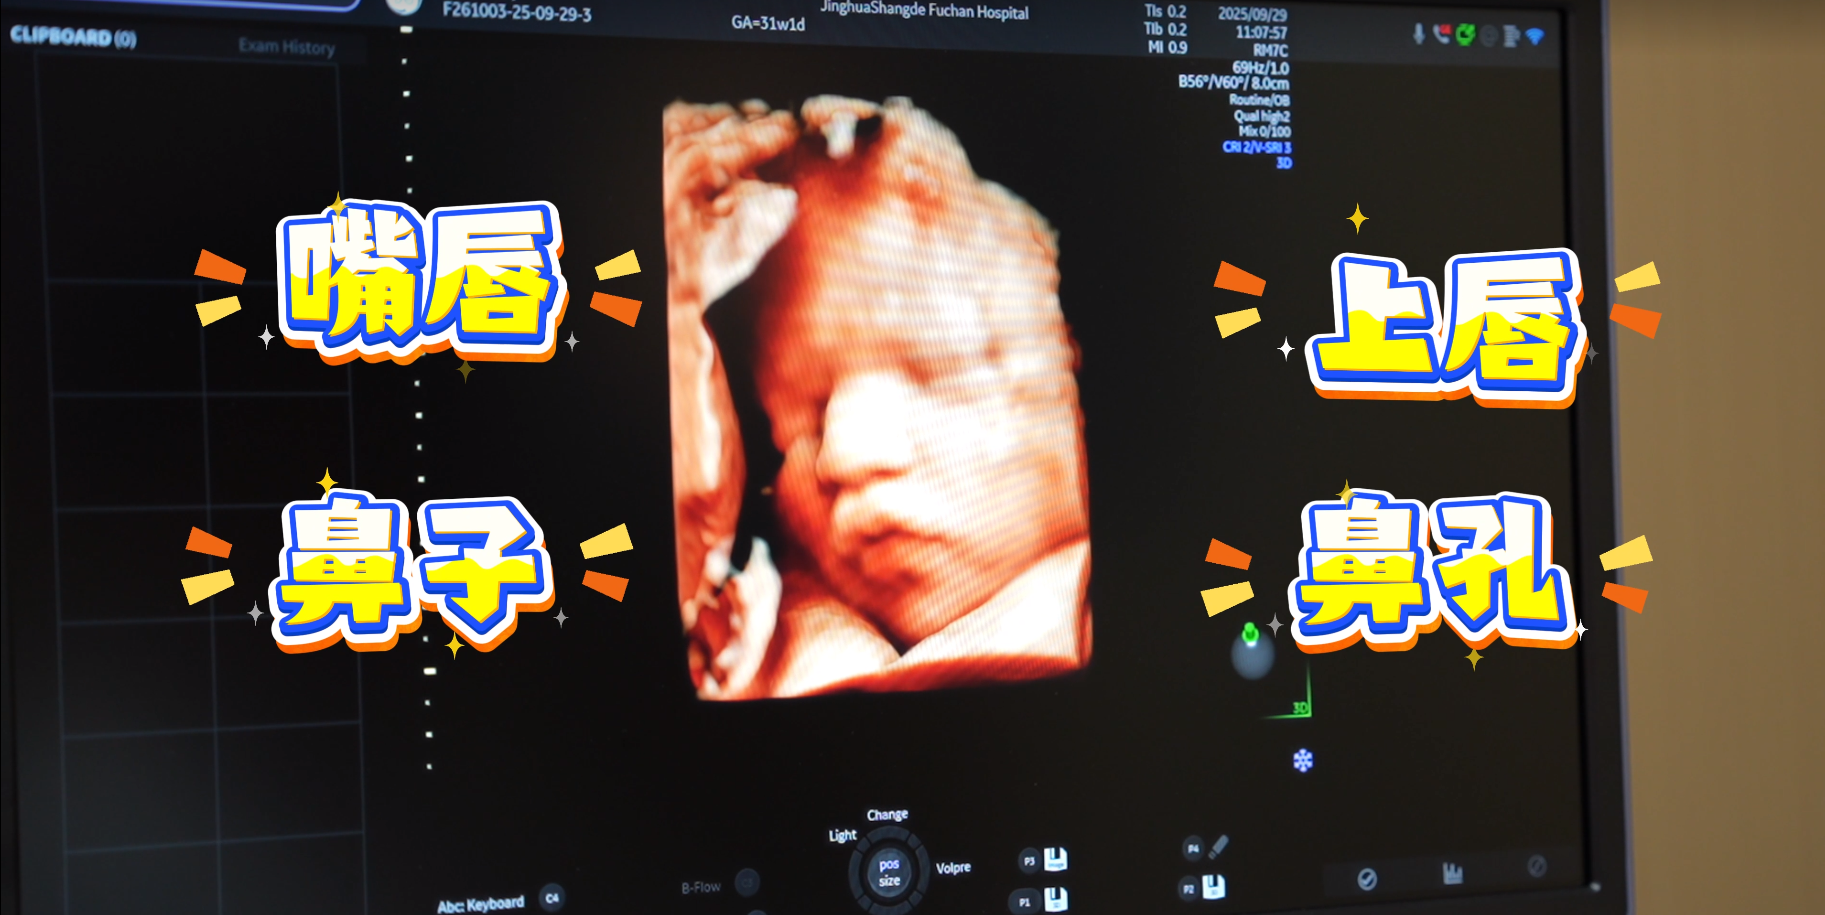

GE-E22四维体验感绝了!见证每一帧清晰瞬间!成像超高清+AI只能筛查+家属同步观看

东北首台「GE-Voluson Expert 22」 四维彩超机器开箱使用